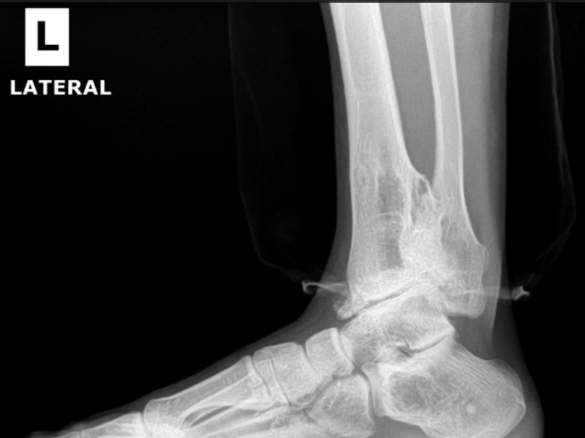

Arthritic flatfoot

Pre-op XR Images